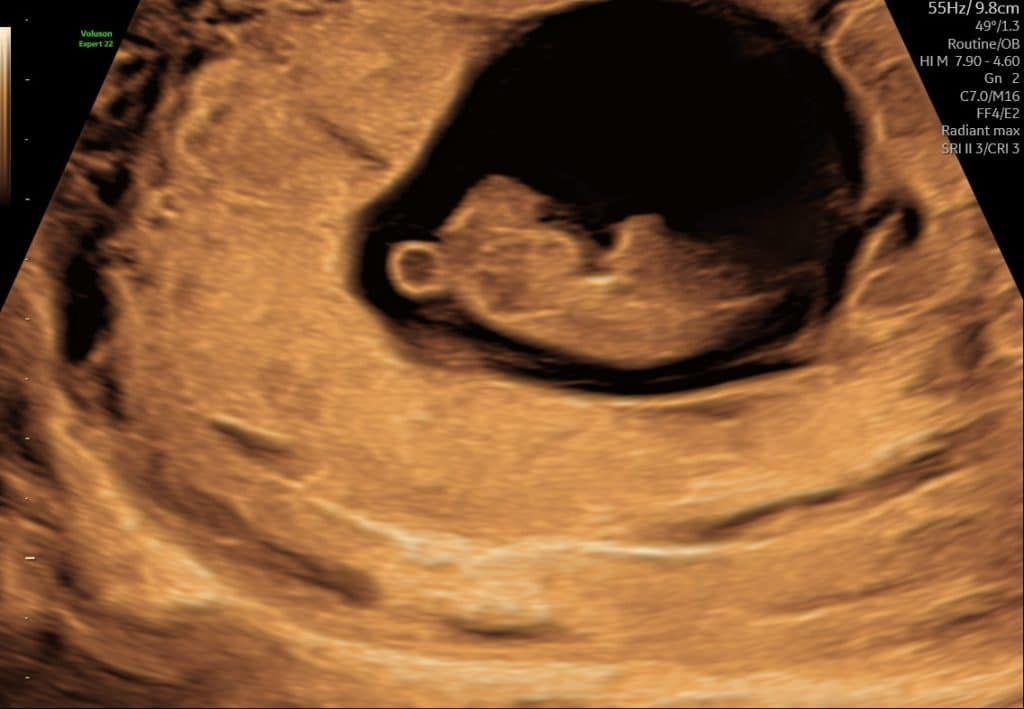

Tidlig scanning uge 6 foster i livmoderen

Tidlig scanning uge 5-6, blommesæk i livmoderen

Eksempel på ultralyd i uge 5–6. Det er normalt, at ikke alle strukturer kan ses på dette tidspunkt.

Nogle gange giver korte ultralydssekvenser et bedre indtryk end stillbilleder alene.

Kort ultralydssekvens fra uge 6 hvor der kan ses blommesæk og tidligt fosteranlæg.